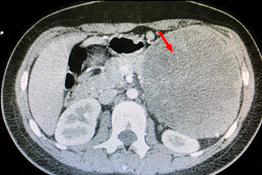

Descrição da figura: Tomografia computadorizada do abdome pós-contraste evidenciando volumosa formação expansiva no corpo e cauda pancreáticos (seta vermelha), medindo 11,2 x 9,2 cm, com captação heterogênea do meio de contraste, determinando compressão do corpo gástrico e deslocamento posterior do rim esquerdo, bem como de suas veias e artérias renais.

• Tomografia computadorizada do abdome: Usualmente demonstra uma lesão bem definida, encapsulada, com variável componente sólido-cístico, podendo existir algumas áreas de degeneração hemorrágica (figura acima);